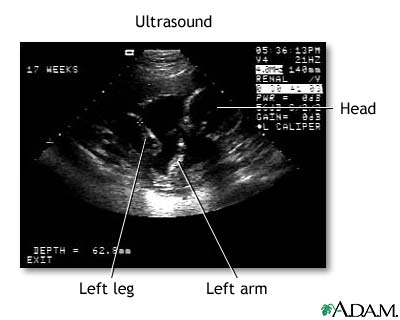

Ultrasound - series: Procedure, part 3

Don't get your hopes up too much about this first, fleeting look at your baby. The black-and-white image you see on the computer screen is grainy, shadowy, and may look more like a test pattern than a baby-to-be. Your sonographer will walk you through what you're seeing by pointing out the fetus' developing heart, limbs, and head.